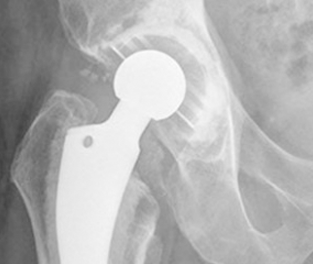

Hip Resurfacing

A hip resurfacing procedure can delay a total hip replacement in younger patients who are likely

to outlive the original implant and require a second surgery later in life. Doctors may also recommend hip resurfacing to improve symptoms of arthritis.

During hip resurfacing, surgeons replace the socket with an artificial cup and resurface the head of the femur instead of removing it. Then they cement a cover that’s usually made of metal on top of the femur. The cover has a short stem that is inserted into the neck of the femur.